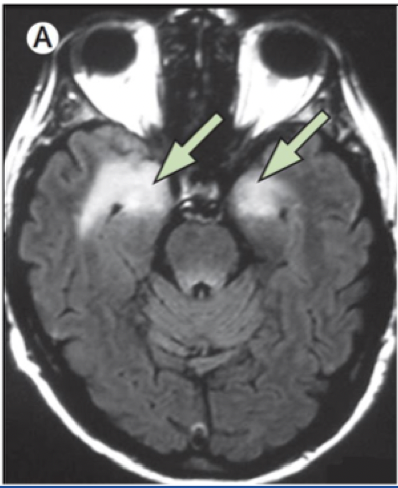

Hva er anti-NMDA receptor encephalitis?

Hva er mesial temporallappsepilepsi?

Form for epilepsi Anfall: - Fokale med autonom/emosjonell/kognitiv aura - Sekundære generaliserte GTK EEG: - Fokal temporal epileptiform aktivitet Etiologi: - Genetisk disposisjon/strukturell/feberkrampe MR: - Hippocampus-sklerose Prognose: - Progresjon -psykososiale problemer - Kir. behandling. 80% anfallsfri